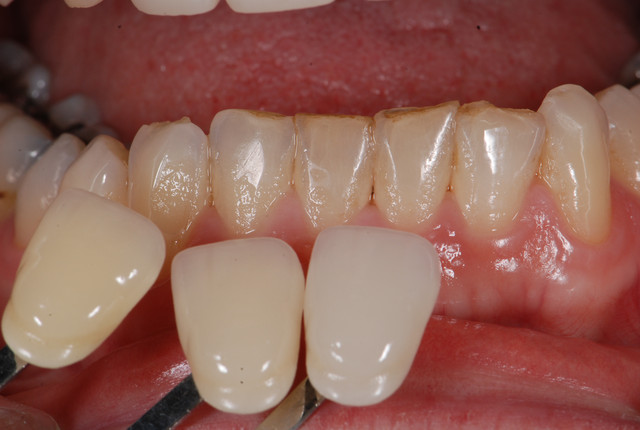

E.max crown try in 280713

#Togias 190713 nora